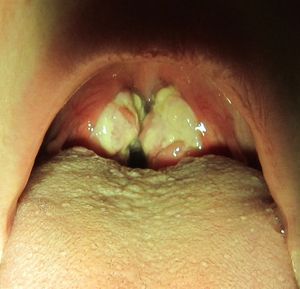

인후염은 상기도 감염으로 발생하는 염증으로, 급성 및 만성으로 분류된다. 급성 인두염은 카타르성, 화농성 또는 궤양성으로, 만성 인두염은 카타르성, 비대성 또는 위축성으로 분류된다. 인두염은 바이러스, 세균, 비감염성 요인에 의해 발생하며, 증상만으로는 바이러스성과 세균성을 구별하기 어려워 인후 배양 검사 등 진단 방법을 활용한다. 치료는 증상 완화에 중점을 두며, 세균성 인두염의 경우 항생제를 사용한다.

편도선염은 인두염의 한 유형이다.[14] 편도와 목의 다른 부분 모두 염증이 있는 경우, '''인두편도염''' 또는 '''편도인두염'''이라고 부를 수 있다.[15] 비인두염(감기)도 인두염의 하위 분류이다.[16]

편도선염은 인두염의 한 유형이다.[14] 염증이 편도와 목의 다른 부분을 모두 포함하는 경우, '''인두편도염''' 또는 '''편도인두염'''이라고 부를 수 있다.[15] 비인두염 (감기)도 인두염의 또 다른 하위 분류이다.[16]